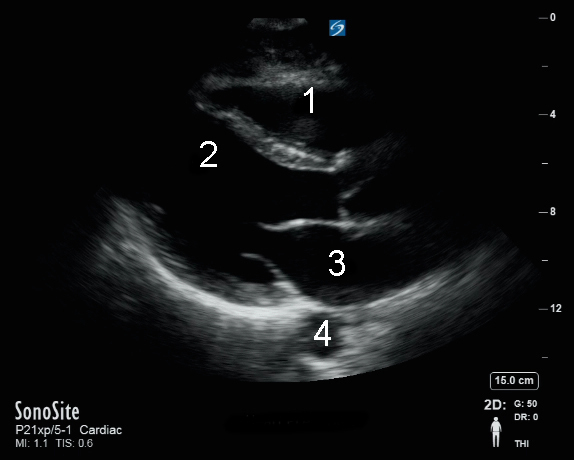

心臓Parasternal Long Axis (PLAX)画像を見る

右心室 (RV)

左心室(LV)

左心房(LA)

大動脈 (Ao)